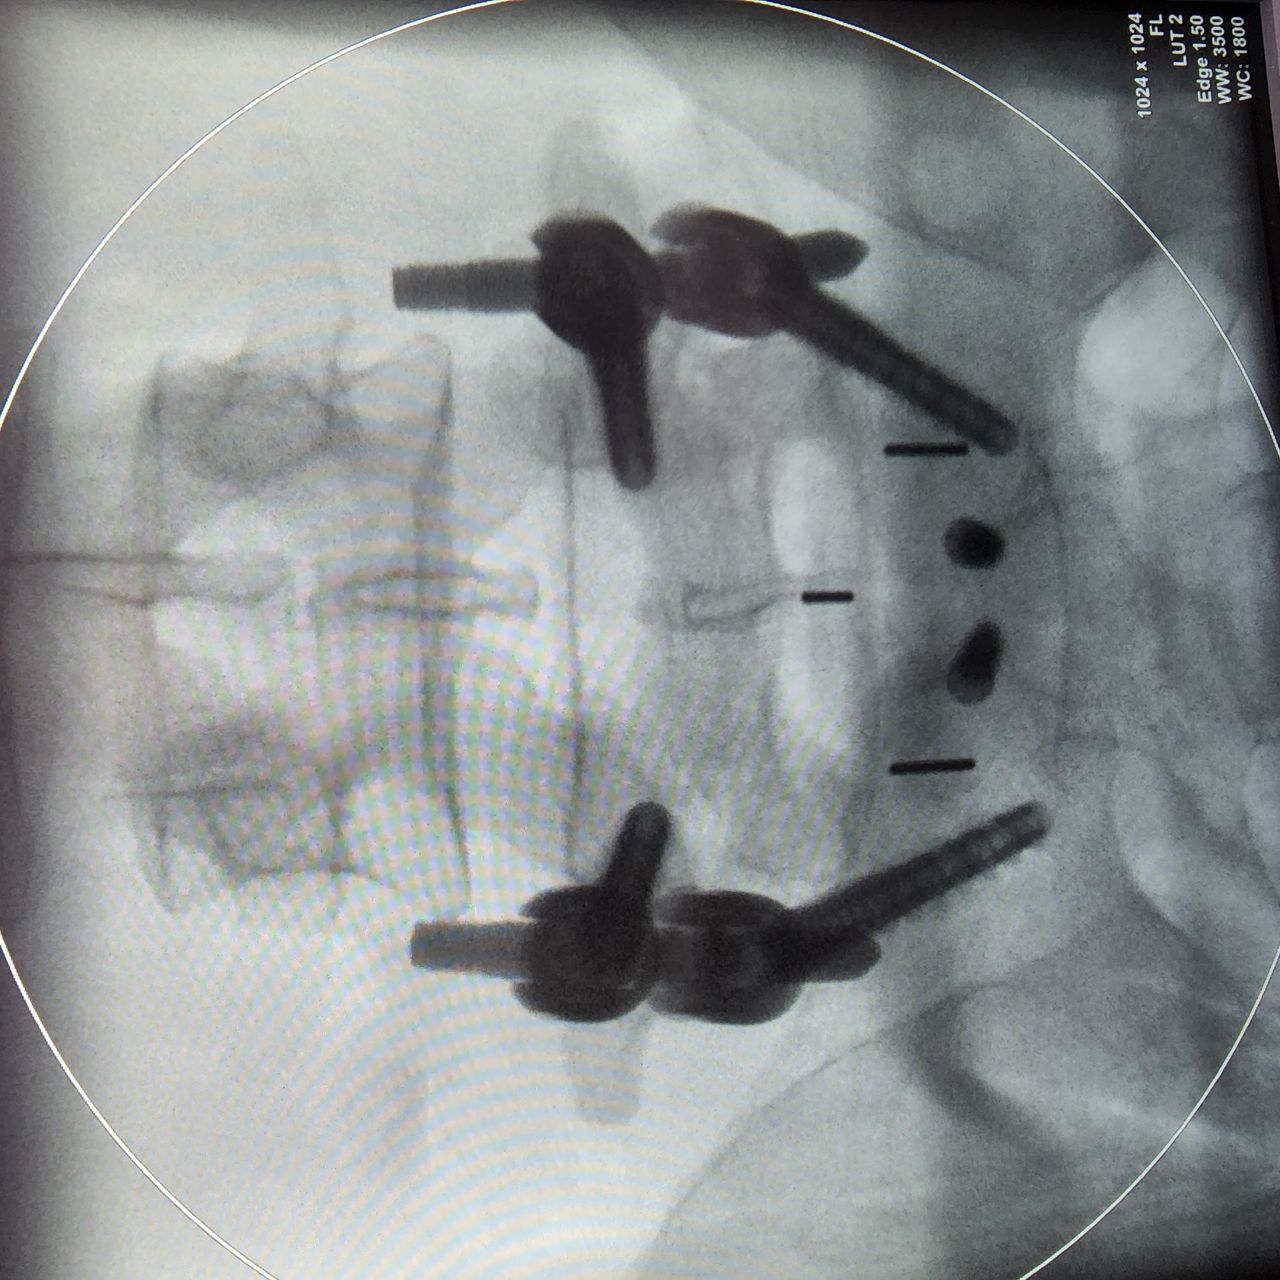

• Alta Especialidad En Cirugía De Columna Vertebral-Privado-San Juan Del Río, Qro 2019-2020.

Presento una Alta Especialidad en Cirugía de Columna Vertebral, con la cual brindo atención para resolver enfermedades como hernias discales, espondilolistesis, tumores óseos vertebrales, fracturas vertebrales, desgaste articular vertebral, deformidades de la alineación de columna vertebral y enfermedades asociadas a nervios en los diferentes segmentos vertebrales.

Cirugía Mínima Invasión de Columna Vertebral

Cirugía Anterior para Fusión Columna Vertebral Lumbar

Cirugía de Fusión para Columna Cervical

Cirugía de cifoplastía, vertebroplastía en caso de fracturas vertebrales.

Cirugía para deformidades de Columna Toraco Lumbar.